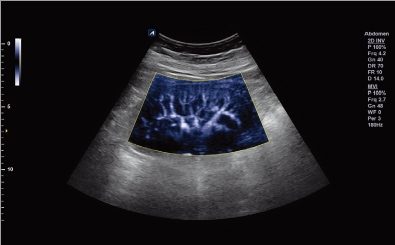

Kidney with MicroView